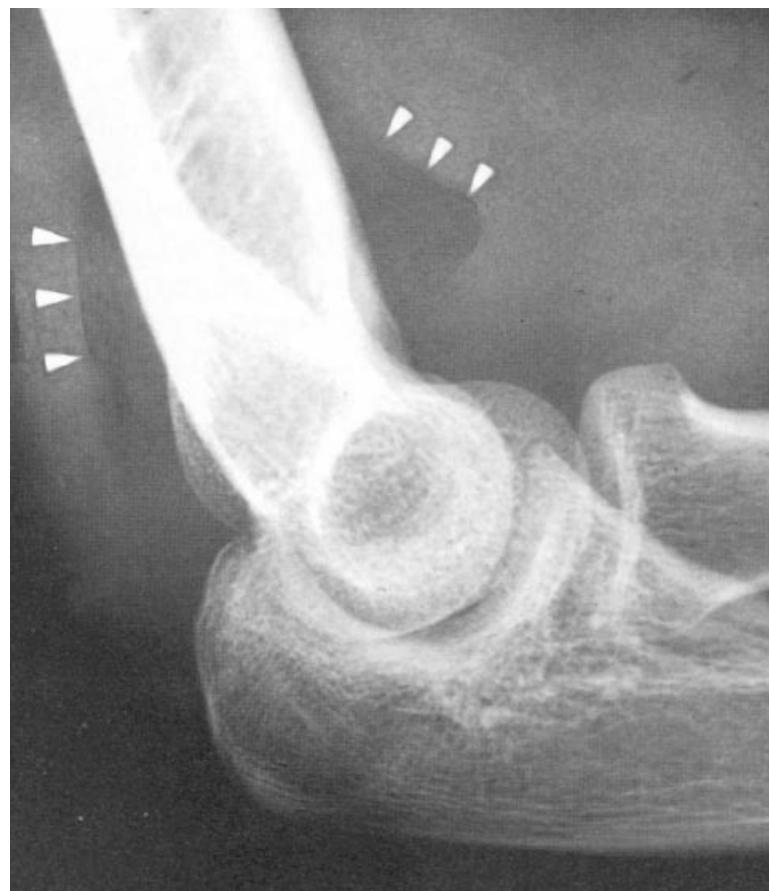

Occult Elbow Fracture (Fat Pad Sign)

- Sign: Positive posterior fat pad sign (always abnormal) or an enlarged anterior fat pad (sail sign).

- Diagnosis: Occult fracture of the elbow (e.g., supracondylar fracture in children or radial head fracture in adults).

- Management: Splinting and orthopedic follow-up; CT may be needed for confirmation.